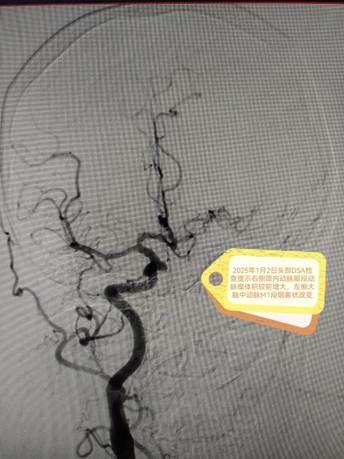

在麻醉科、手术室等多科室通力配合下,丁昊主任团队凭借丰富的经验与精湛的技术,顺利完成两阶段高难度手术。术后,李阿姨恢复良好,未出现神经功能损伤,脑血流显著改善,动脉瘤成功隔绝。护理团队全程实施个性化康复计划,从病情观察到心理疏导,从功能锻炼到生活护理,以专业与温情助力患者快速康复。

术后DSA结果